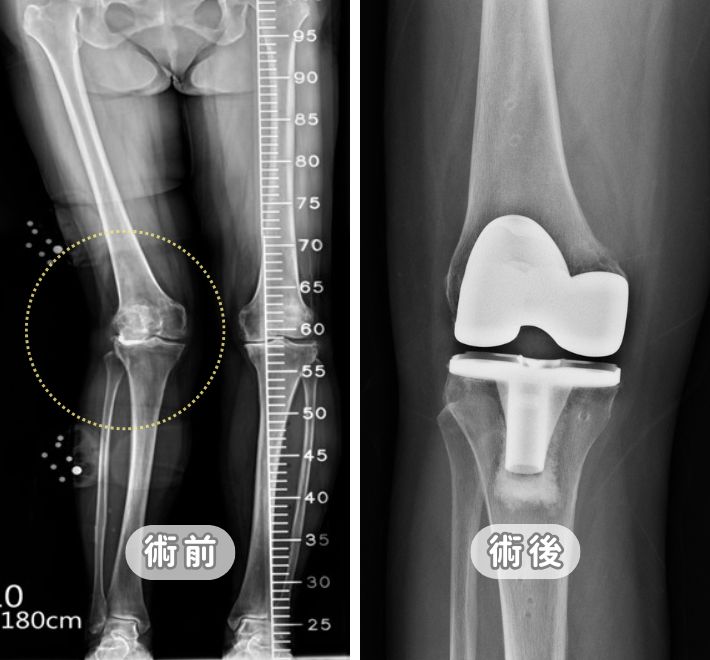

「全膝」人工膝關節置換 (TKR):針對全磨損與嚴重變形的最終方案

當內、外側關節面皆受損,或伴隨嚴重的骨骼變形,則需採用全膝置換。這是一種成熟且成功率高的手術,能徹底解決因磨損產生的機械性劇痛。